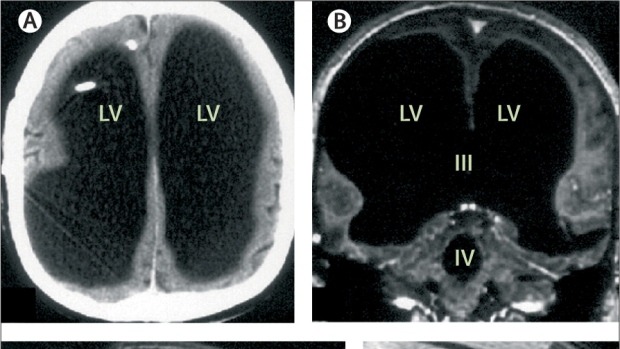

First documented in the medical journal The Lancet in 2007, the case involved a middle-aged man whose brain scans revealed something extraordinary—most of his skull appeared to be filled with fluid, leaving only a thin layer of brain tissue.

He only sought medical help after experiencing mild weakness in his leg. What doctors found during imaging was unexpected: his brain had been severely compressed over decades.

The condition behind this was hydrocephalus—a disorder in which fluid accumulates in the brain. He had been diagnosed as an infant and treated, but after the removal of a shunt in his teenage years, the fluid gradually built up again.

Early interpretations of the case suggested that up to 90% of his brain was “missing.” Later clarification showed that the brain tissue was still present—but squeezed into a thin outer layer.